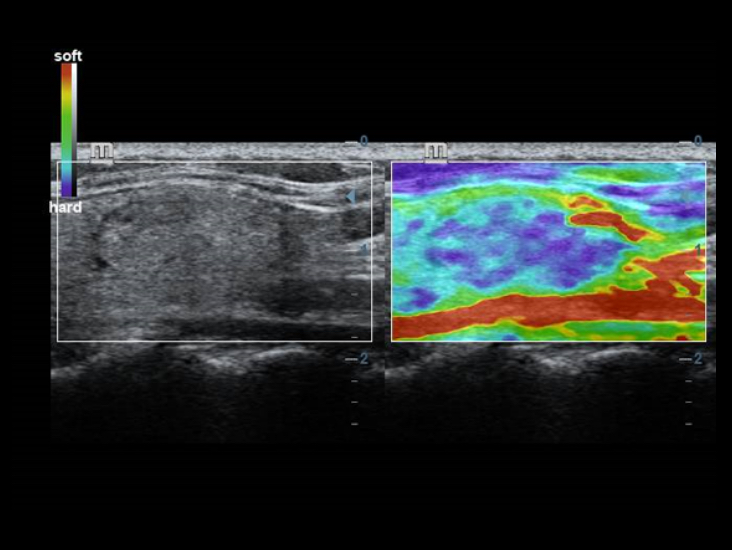

Hervorragende Detailaufl?sung

Unsere Motivation bei Mindray ist es, die moderne Medizintechnik durch zukunftsorientierte Techno-logien zu verbessern. Mit seinem Full HD-Monitor, bew?hrten Ultraschalltechnologien und einer optimierten Schallkopf-Familie bietet das DC-40 mit Full HD eine hervorragende Bildqualit?t. Sie verbessert ein breites Spektrum klinischer Anwendungen.

Diese bew?hrten Ultraschalltechnologien sorgen f├╝r eine h?here Diagnosequalit?t:

Der Einsatz anerkannter Bildgebungstechnologien macht das DC-40 mit Full HD sehr leistungsstark und hochwertig. Sie sind erfolgreich aus etablierten Ultraschallsystemen migriert worden. Eine clevere Kombination von Ultraschallsonden mit spezialisierten Schallk?pfen unterst├╝tzt erstklassige Ergebnisse in einem breiten Anwendungsspektrum. Mit Hilfe der Breitband-Schallk?pfe l?sst sich eine Vielzahl an Patiententypen erfolgreich untersuchen.